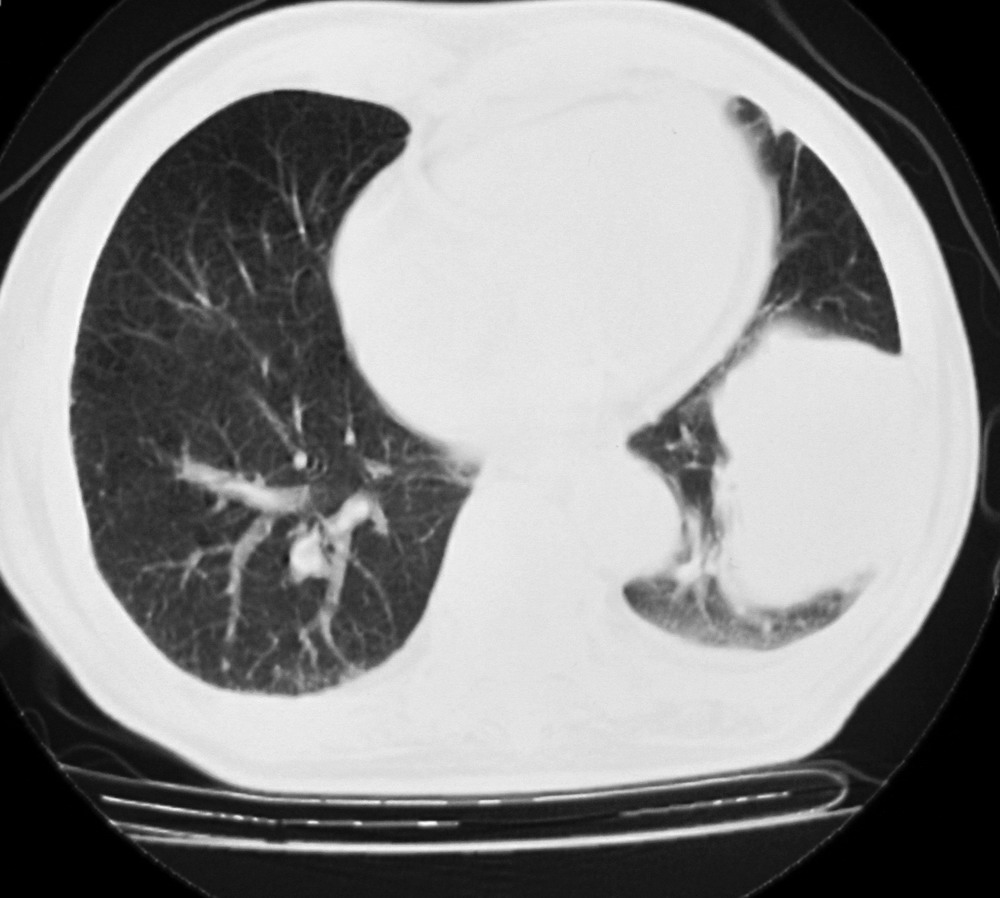

女,78,胸痛3个月,余无特殊。

1)左肺下叶软组织肿块,不排除周围型肺癌可能。2)左侧少量胸腔积液。3)心包积液。4)冠状动脉及主动脉钙化。

结果:肺癌